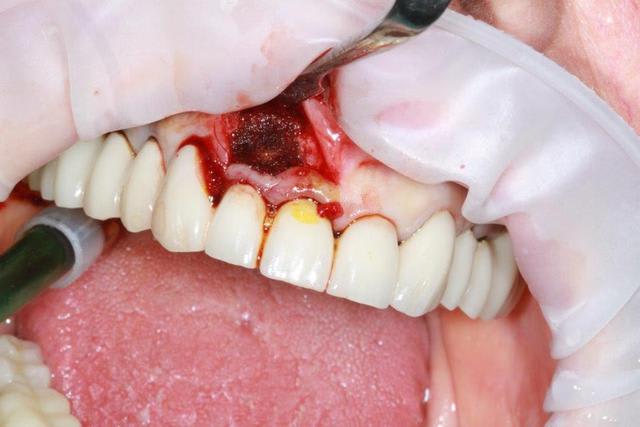

08/04/2016 à 15h05

zut, zut, zut...petit soucis ce matin abcès sur 12, j'ouvre et la racine est fendue, donc résection, curetage soigneux éponges de gelatemp et sutures.

Prévision de greffe future, à suivre...

Img 3855 wpsmpq - Eugenol

Img 3856 bdrcjd - Eugenol

Img 3857 zgbcyd - Eugenol